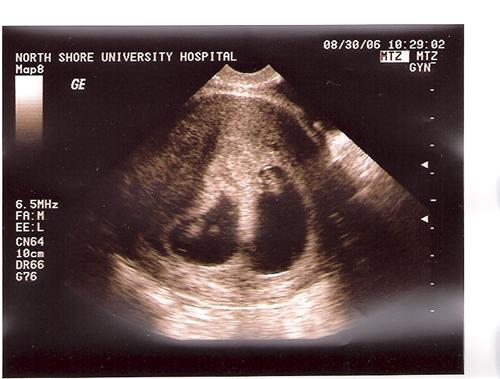

Good news... now w/ 7.5 week sono pic

As some of you may remember from last week one of my twin's heartbeat was measuring a bit weaker than the other.

Well, we went back to North Shore Univ Hospital today (Center for Human Reproduction) and all is fine. He/She must have caught up.